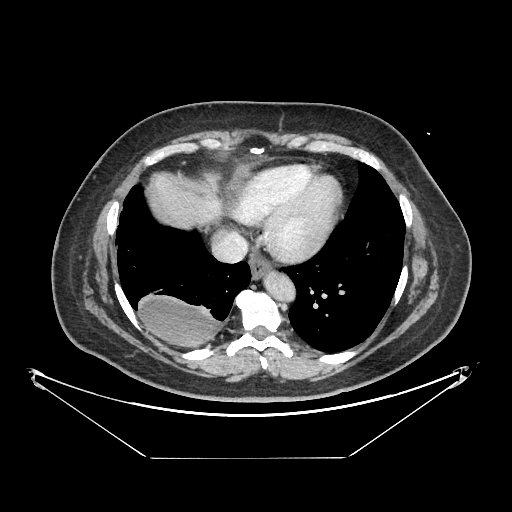

Image Grid

4Γ—3 grid: Rows show different image types (Original NATIVE, Reconstructed NATIVE, Original VENOUS, Generated VENOUS), Columns show windowing techniques (No Window, Lung Window, Mediastinum Window)

Original VENOUS CT scan

Full window (WL 1023.5, WW 4095 β†’ Low βˆ’1024, High +3071)

Lung window (WL -600, WW 1500 β†’ Low βˆ’1350, High +150)

Mediastinum window (WL 40, WW 400 β†’ Low βˆ’160, High +240)